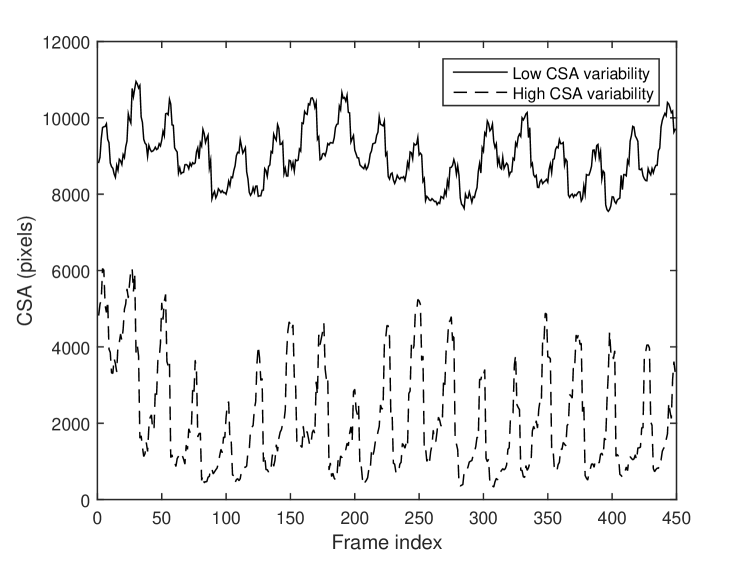

Determination of relative changes in circulating blood volume is important for a variety of acute and chronic medical conditions including hemorrhage from trauma, septic shock, dialysis and volume overload pertaining to congestive heart failure [1, 2, 3, 4, 5]. The estimation of absolute blood volume, while ideal, remains a significant challenge [6]. Recent studies suggest that non-invasive measures such as transverse ultrasound (cross-section area, CSA) of the internal jugular vein (IJV) can be used to detect and monitor relative changes in blood volume [7, 8]. As shown in Fig 1, the CSA of the IJV is dynamic with spatial and temporal variations that can correlate with relative changes in volume status. Short-term variability reflects a variety of factors including blood volume, proximity to the carotid artery, cardiac contractility, respiratory effort and local anatomy. Changes in parameters over the long-term can reflect relative changes in blood volume. Demonstration of short- and long-term CSA variability of a healthy patient sitting at different angles of inclination to simulate relative changes in circulating blood volume is shown in Fig. 2. Accurate segmentation and tracking of the rapidly changing IJV is fundamental to the use of ultrasound to estimate relative changes in blood volume.